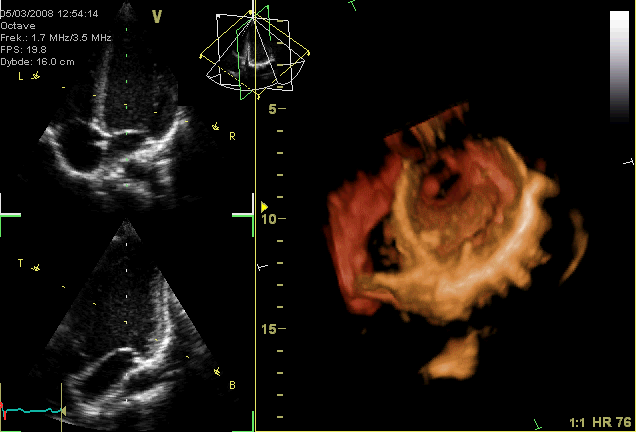

Echocardiography, also known as cardiac ultrasound, is the use of ultrasound to examine the heart. It is a type of medical imaging, using standard ultrasound or Doppler ultrasound. The visual image formed using this technique is called an echocardiogram, a cardiac echo, or simply an echo. Echocardiography is routinely used in the diagnosis, management, and follow-up of patients with any suspected or known heart diseases. It is one of the most widely used diagnostic imaging modalities in cardiology. It can provide a wealth of helpful information, including the size and shape of the heart (internal chamber size quantification), pumping capacity, location and extent of any tissue damage, and assessment of valves. An echocardiogram can also give physicians other estimates of heart function, such as a calculation of the cardiac output, ejection fraction, and diastolic function (how well the heart relaxes). Echocardiography is an important tool in assessing wall motion abnormality in patients with suspected cardiac disease. It is a tool which helps in reaching an early diagnosis of myocardial infarction, showing regional wall motion abnormality. Also, it is important in treatment and follow-up in patients with heart failure, by assessing ejection fraction. Echocardiography can help detect cardiomyopathies, such as hypertrophic cardiomyopathy, and dilated cardiomyopathy. The use of stress echocardiography may also help determine whether any chest pain or associated symptoms are related to heart disease. The biggest advantage of echocardiography is that it is not invasive (does not involve breaking the skin or entering body cavities) and has no known risks or side effects. Not only can an echocardiogram create ultrasound images of heart structures, but it can also produce accurate assessment of the blood flowing through the heart by Doppler echocardiography, using pulsed- or continuous-wave Doppler ultrasound. This allows assessment of both normal and abnormal blood flow through the heart.